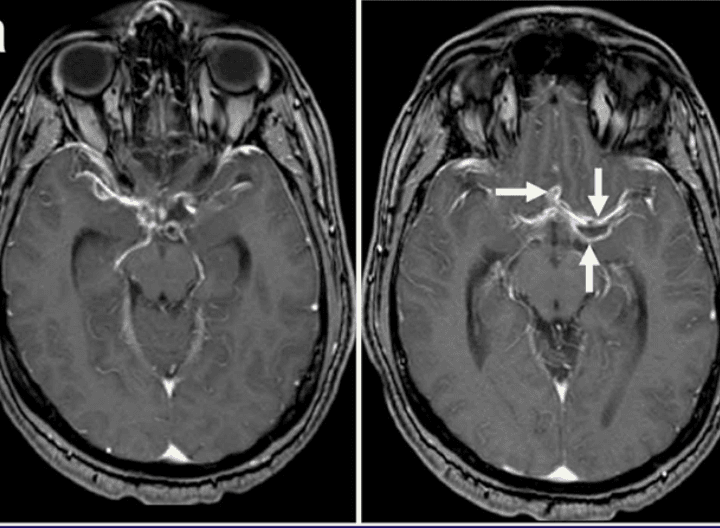

Laboratory studies show a white blood cell count of 6.8 x 10^9/L, hemoglobin 14.1 g/dL, platelets 248 x 10^9/L, sodium 138 mmol/L, creatinine 0.9 mg/dL, and glucose 96 mg/dL. Liver enzymes are normal. Noncontrast head CT shows multiple small parenchymal calcifications. HIV fourth-generation testing is pending. CT angiography demonstrates patent cerebral arteries. Brain MRI reveals dilatation of the suprasellar and Sylvian cisterns with septated fluid-filled subarachnoid cystic lesions surrounding the proximal middle cerebral arteries, peripheral enhancement after gadolinium, and an old lacunar infarct adjacent to one of the cysts.

Brain MRI showing enlarged basal cisterns, peripheral enhancement, and septated subarachnoid cystic lesions.